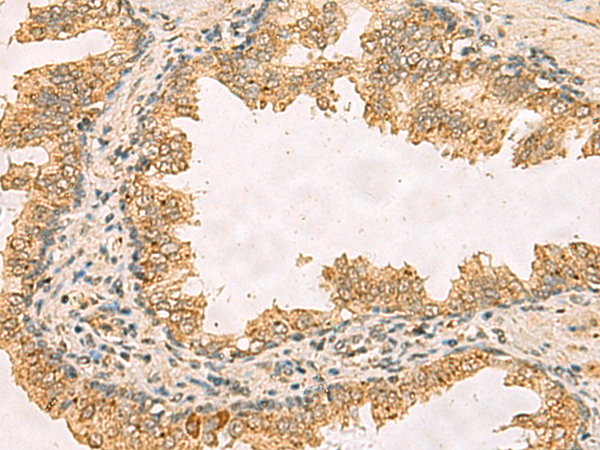

分类: 科研抗体货号: P02831别名: BDMF; MSAP; DMSFH; LGMBF; DMSMFH; c86fus; HEL-249应用: IHC反应种属: Human

分类: 科研抗体货号: P02786别名: ERFAD应用: WB,IHC反应种属: Human

分类: 科研抗体货号: P02862别名: RPL10_5_1358应用: WB,IHC反应种属: Human, Mouse